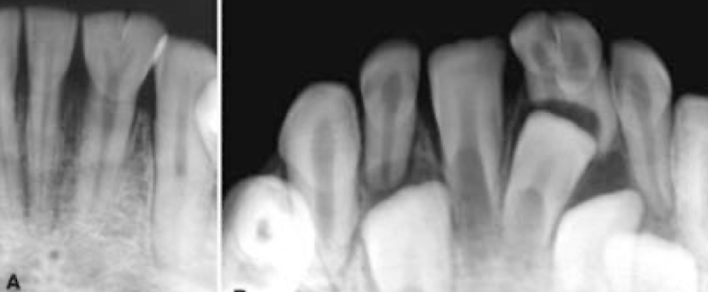

Based on this xray, what developmental and congenital abnormality is observed?

a. number of teeth

b. size of teeth

c. eruption of teeth

d. morphology of teeth